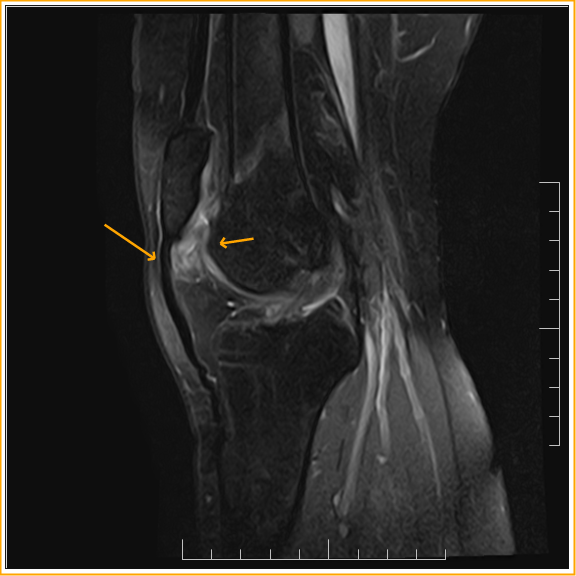

From mungfali.com

MRI Fat Pad Impingement Knee Fat Pad Syndrome Knee Treatment Ice or cryotherapy to reduce pain and. Learn about the fat pads of the knee. Usually, we start with simple treatments. Acute or chronic inflammation of the infrapatellar fat pad (ifp) is a common source of anterior knee pain; If the fat pat behind your kneecap becomes pinched between the bones of your knee, you might develop infrapatellar fat pad. Fat Pad Syndrome Knee Treatment.

From radedasia.com

KNEE MRI FAT PAD IMPINGEMENT WHERE TO LOOK & WHAT TO LOOK FOR Radedasia Fat Pad Syndrome Knee Treatment Rest and avoid aggravating activities. Ice or cryotherapy to reduce pain and. Usually, we start with simple treatments. Learn about the fat pads of the knee. Also called hoffa's disease, fat pad. If the fat pat behind your kneecap becomes pinched between the bones of your knee, you might develop infrapatellar fat pad syndrome. Acute or chronic inflammation of the. Fat Pad Syndrome Knee Treatment.